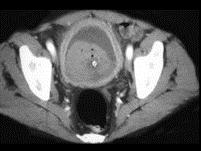

女,36岁,血尿1周余,请根据所示图像,选择最可能诊断 ( )A、膀胱癌B、输尿管癌C、膀胱结石D、膀胱息肉E、膀胱血块

问题 女,36岁,血尿1周余,请根据所示图像,选择最可能诊断 ( )

选项 A、膀胱癌 B、输尿管癌 C、膀胱结石 D、膀胱息肉 E、膀胱血块

答案 E